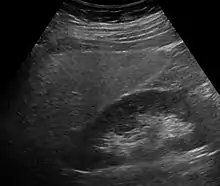

Imaging studies are often obtained during the evaluation process. Ultrasonography reveals a "bright" liver with increased echogenicity. Medical imaging can aid in diagnosis of fatty liver; fatty livers have lower density than spleens on computed tomography (CT), and fat appears bright in T1-weighted magnetic resonance images (MRIs). Magnetic resonance elastography, a variant of magnetic resonance imaging, is investigated as a non-invasive method to diagnose fibrosis progression.[28] Histological diagnosis by liver biopsy is the most accurate measure of fibrosis and liver fat progression as of 2018.[6] Conventional imaging methods, such as ultrasound, CT and MRI, are not specific enough to detect fatty liver disease unless fat occupies at least 30% of the liver volume.[29]